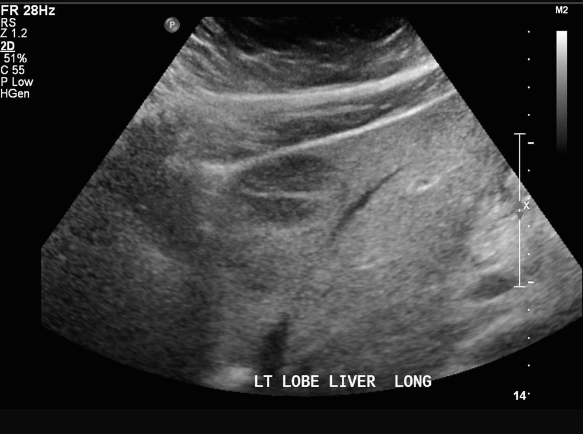

FNH (Focal Nodular hyperplasia) US finding

- hypoechoic lesion with central scar

- fatty liver